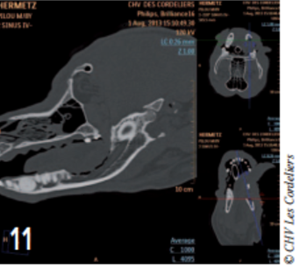

L’ostectomie allait en profondeur jusqu’au canal mandibulaire (photos 9 à 12).

Photo 11 : Coupe sagittale de l’image tomodensitométrique postopératoire montrant l’étendue de l’ostectomie.